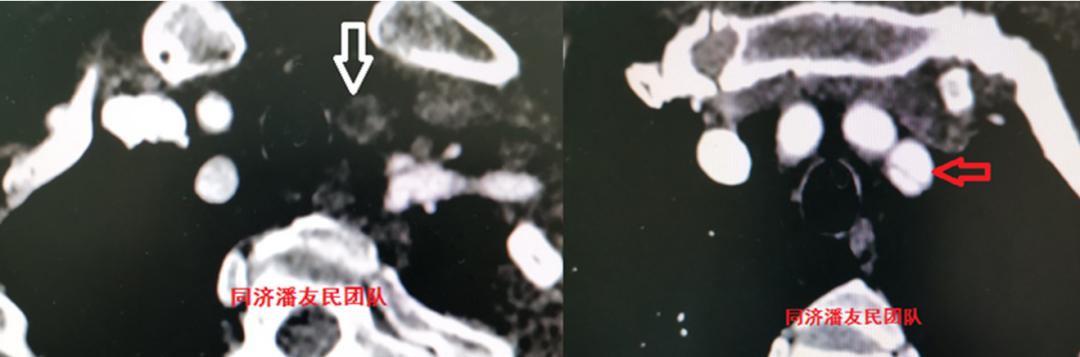

于是,胸腹主动脉CTA被安排(图3~5),结果显示夹层病变从升主动脉远端开始,累及到主动脉弓部,其中左颈总动脉及左锁骨下动脉均累及。